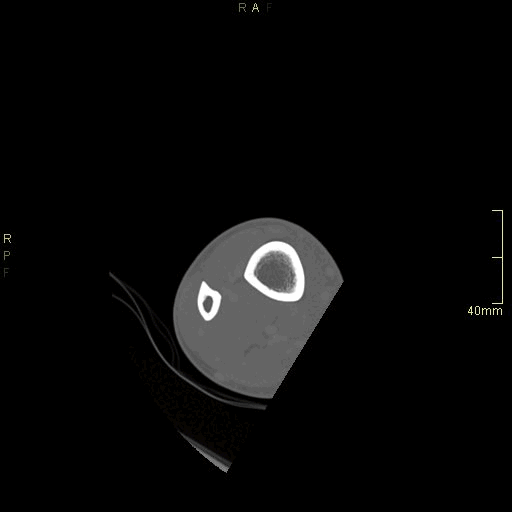

CT Ankle Contrast- Soft tissue window (axial)

CT Ankle Contrast- Bone window (axial)